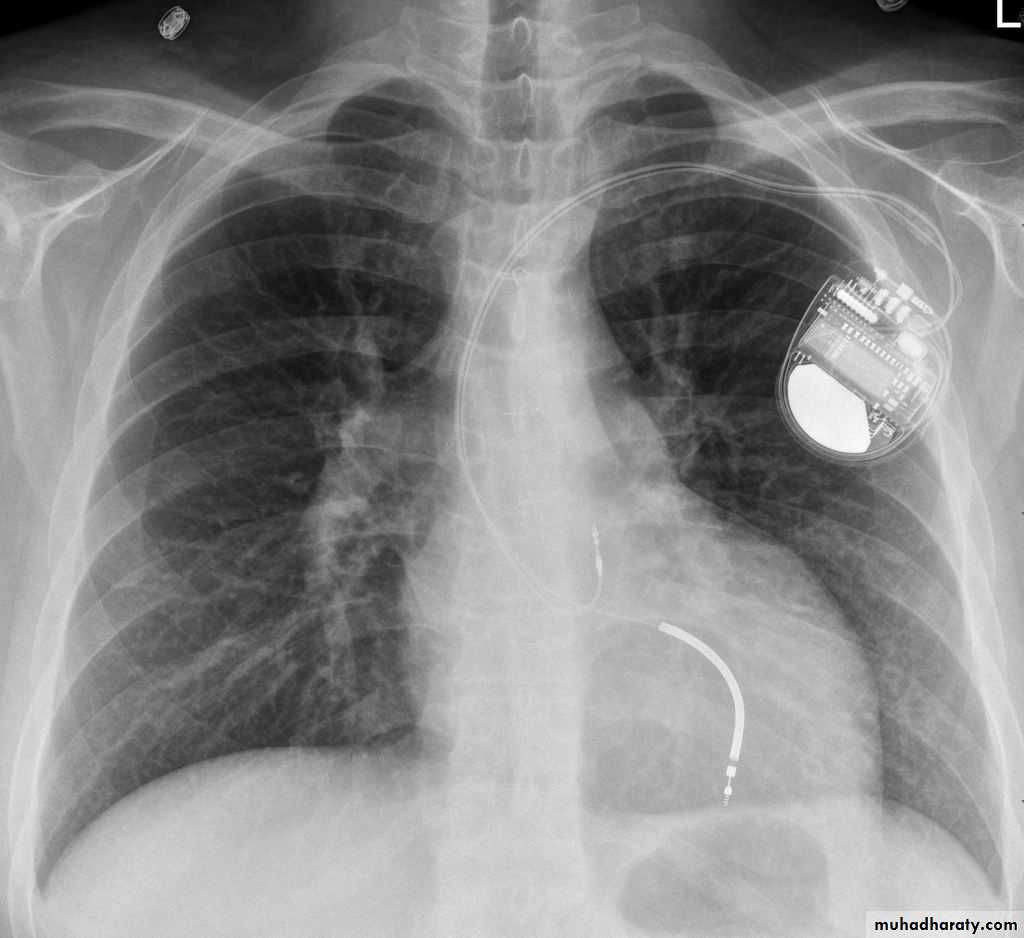

• Check up chest x-ray